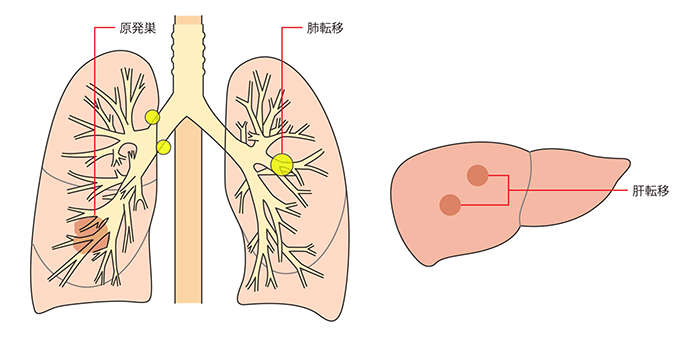

何らかの原因によって遺伝子に異常が起こり、そのことで限りなく増え続け(増殖)、別の場所に移動(転移)してしまう細胞を「がん細胞」といいます。がん細胞は増殖してまわりの臓器に影響を与え、また、身体のあちこちに転移して他の臓器にも影響を与えるようになります。

一般に「肺がん」とは肺から始まったものをいい、正確には「原発性肺がん」と呼びます。これに対して、たとえば乳がん、大腸がんなど他の臓器から始まって肺に転移を起こした場合は「転移性肺腫瘍」と呼び、原発性肺がんとは違う扱いをします。

また、がん細胞は、増え続けるだけでなく、周囲に広がったり(浸潤)、他の臓器に移ったり(転移)して新しいがんを作る特徴があります。

転移とは、がん細胞が別の部位に移動し、そこで増えることをいいます。

がん細胞は、血液やリンパ液の流れにのって移動し、行き着いた先で増えていきます。

肺には多くの血管やリンパ管が集まっているため、肺からほかの部位への転移、ほかの部位にできたがんから肺への転移、どちらも起きやすいといえます。

原発性肺がんと転移性肺腫瘍

最初に肺にできたがんは「原発性肺がん」、ほかの部位にできたがんが肺に転移したものは「転移性肺腫瘍」と呼ばれます。

たとえば、大腸がんが肺へ転移したら、“大腸がんを原発とする転移性肺腫瘍(大腸がんの肺転移)”、肺がんが脳へ転移したら、“肺がんを原発とする転移性脳腫瘍(肺がんの脳転移)”です。

転移性肺腫瘍は、元のがんの性質をもっているので、原発性肺がんとは治療方針が異なります。このため、原発性か転移性かを見分けることはとても大切です。

初めて肺にがんが発見されたときは原発性肺がんである可能性が高いのですが、ほかの部位にがんがある場合や、以前、ほかのがんにかかったことがある場合は転移性肺腫瘍の可能性もあります。転移性肺腫瘍は、病巣が2個以上であることが少なくありません。

原発性か転移性かを見分けるには、採取した肺のがん細胞と、ほかの部位または以前かかったがんのがん細胞とを比較し、形状や種類、遺伝子の状況などを確認します。

肺がんの転移の種類

転移は、方法によって血行性転移、リンパ行性転移、播種性転移に分けられます。

血行性転移は、血液の流れにのってがん細胞が移動し、転移を起こすことです。

リンパ行性転移は、リンパ液が集まるリンパ節という部位にがんが転移し、そこからリンパ液の流れにのってほかのリンパ節へとがん細胞が広がることです。

播種性転移とは、胸部の空間(胸腔)や腹部の空間(腹腔)にがん細胞がばらまかれるように広がることです。

肺には多くの血管とリンパ管が集まっているので、肺がんは血行性、リンパ行性に転移しやすく、特に脳、骨、肝臓、副腎、リンパ節などが好発部位です。